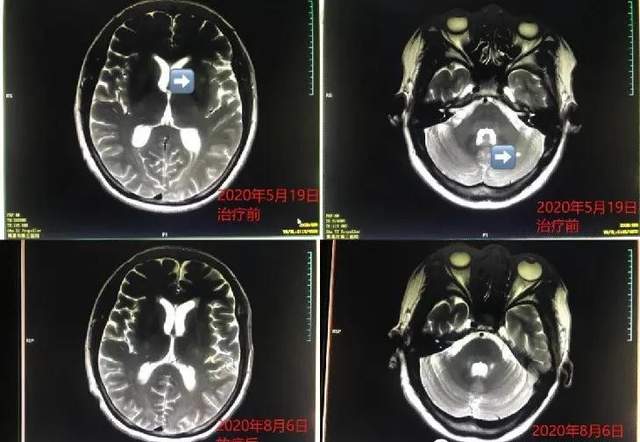

脑转移放疗后病灶几乎消失